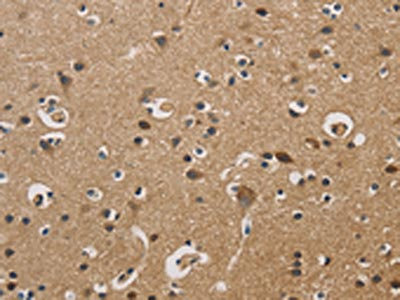

The image on the left is immunohistochemistry of paraffin-embedded Human brain tissue using CSB-PA929092(DUSP23 Antibody) at dilution 1/20, on the right is treated with fusion protein. (Original magnification: ×200)